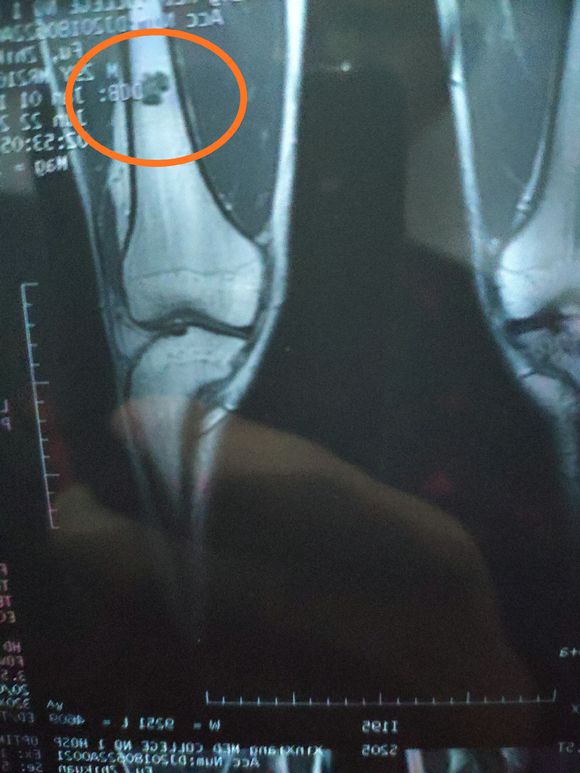

一路向北 02019-01-28 患者家属我孩子今年15岁,年初查出骨肉瘤,左腿关节处,化疗5次做载肢,手术后伤口感染误了化疗,两个多月快三个月发生肺转,如今刚住...